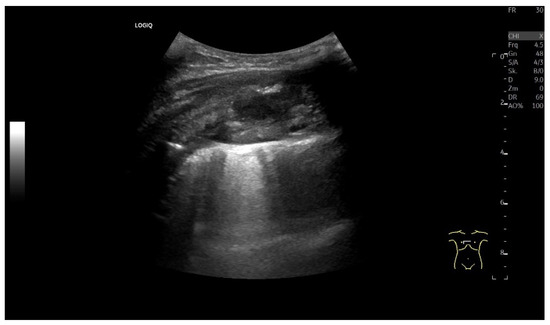

| Mesothelial cysts | Typical cyst criteria. If the content is hypoechoic and not anechoic due to near-field artifacts, CEUS is helpful. Non-enhanced in CEUS. |